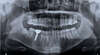

Un bilan dentaire doit être réalisé avant le début du traitement afin de s’assurer qu’il n’existe ni carie, ni gingivite, ni déchaussement des dents en évolution.

Un bilan dentaire doit être réalisé avant le début du traitement afin de s’assurer qu’il n’existe ni carie, ni gingivite, ni déchaussement des dents en évolution. Dans le cas contraire, ces troubles sont à traiter avant le début du traitement orthodontique.